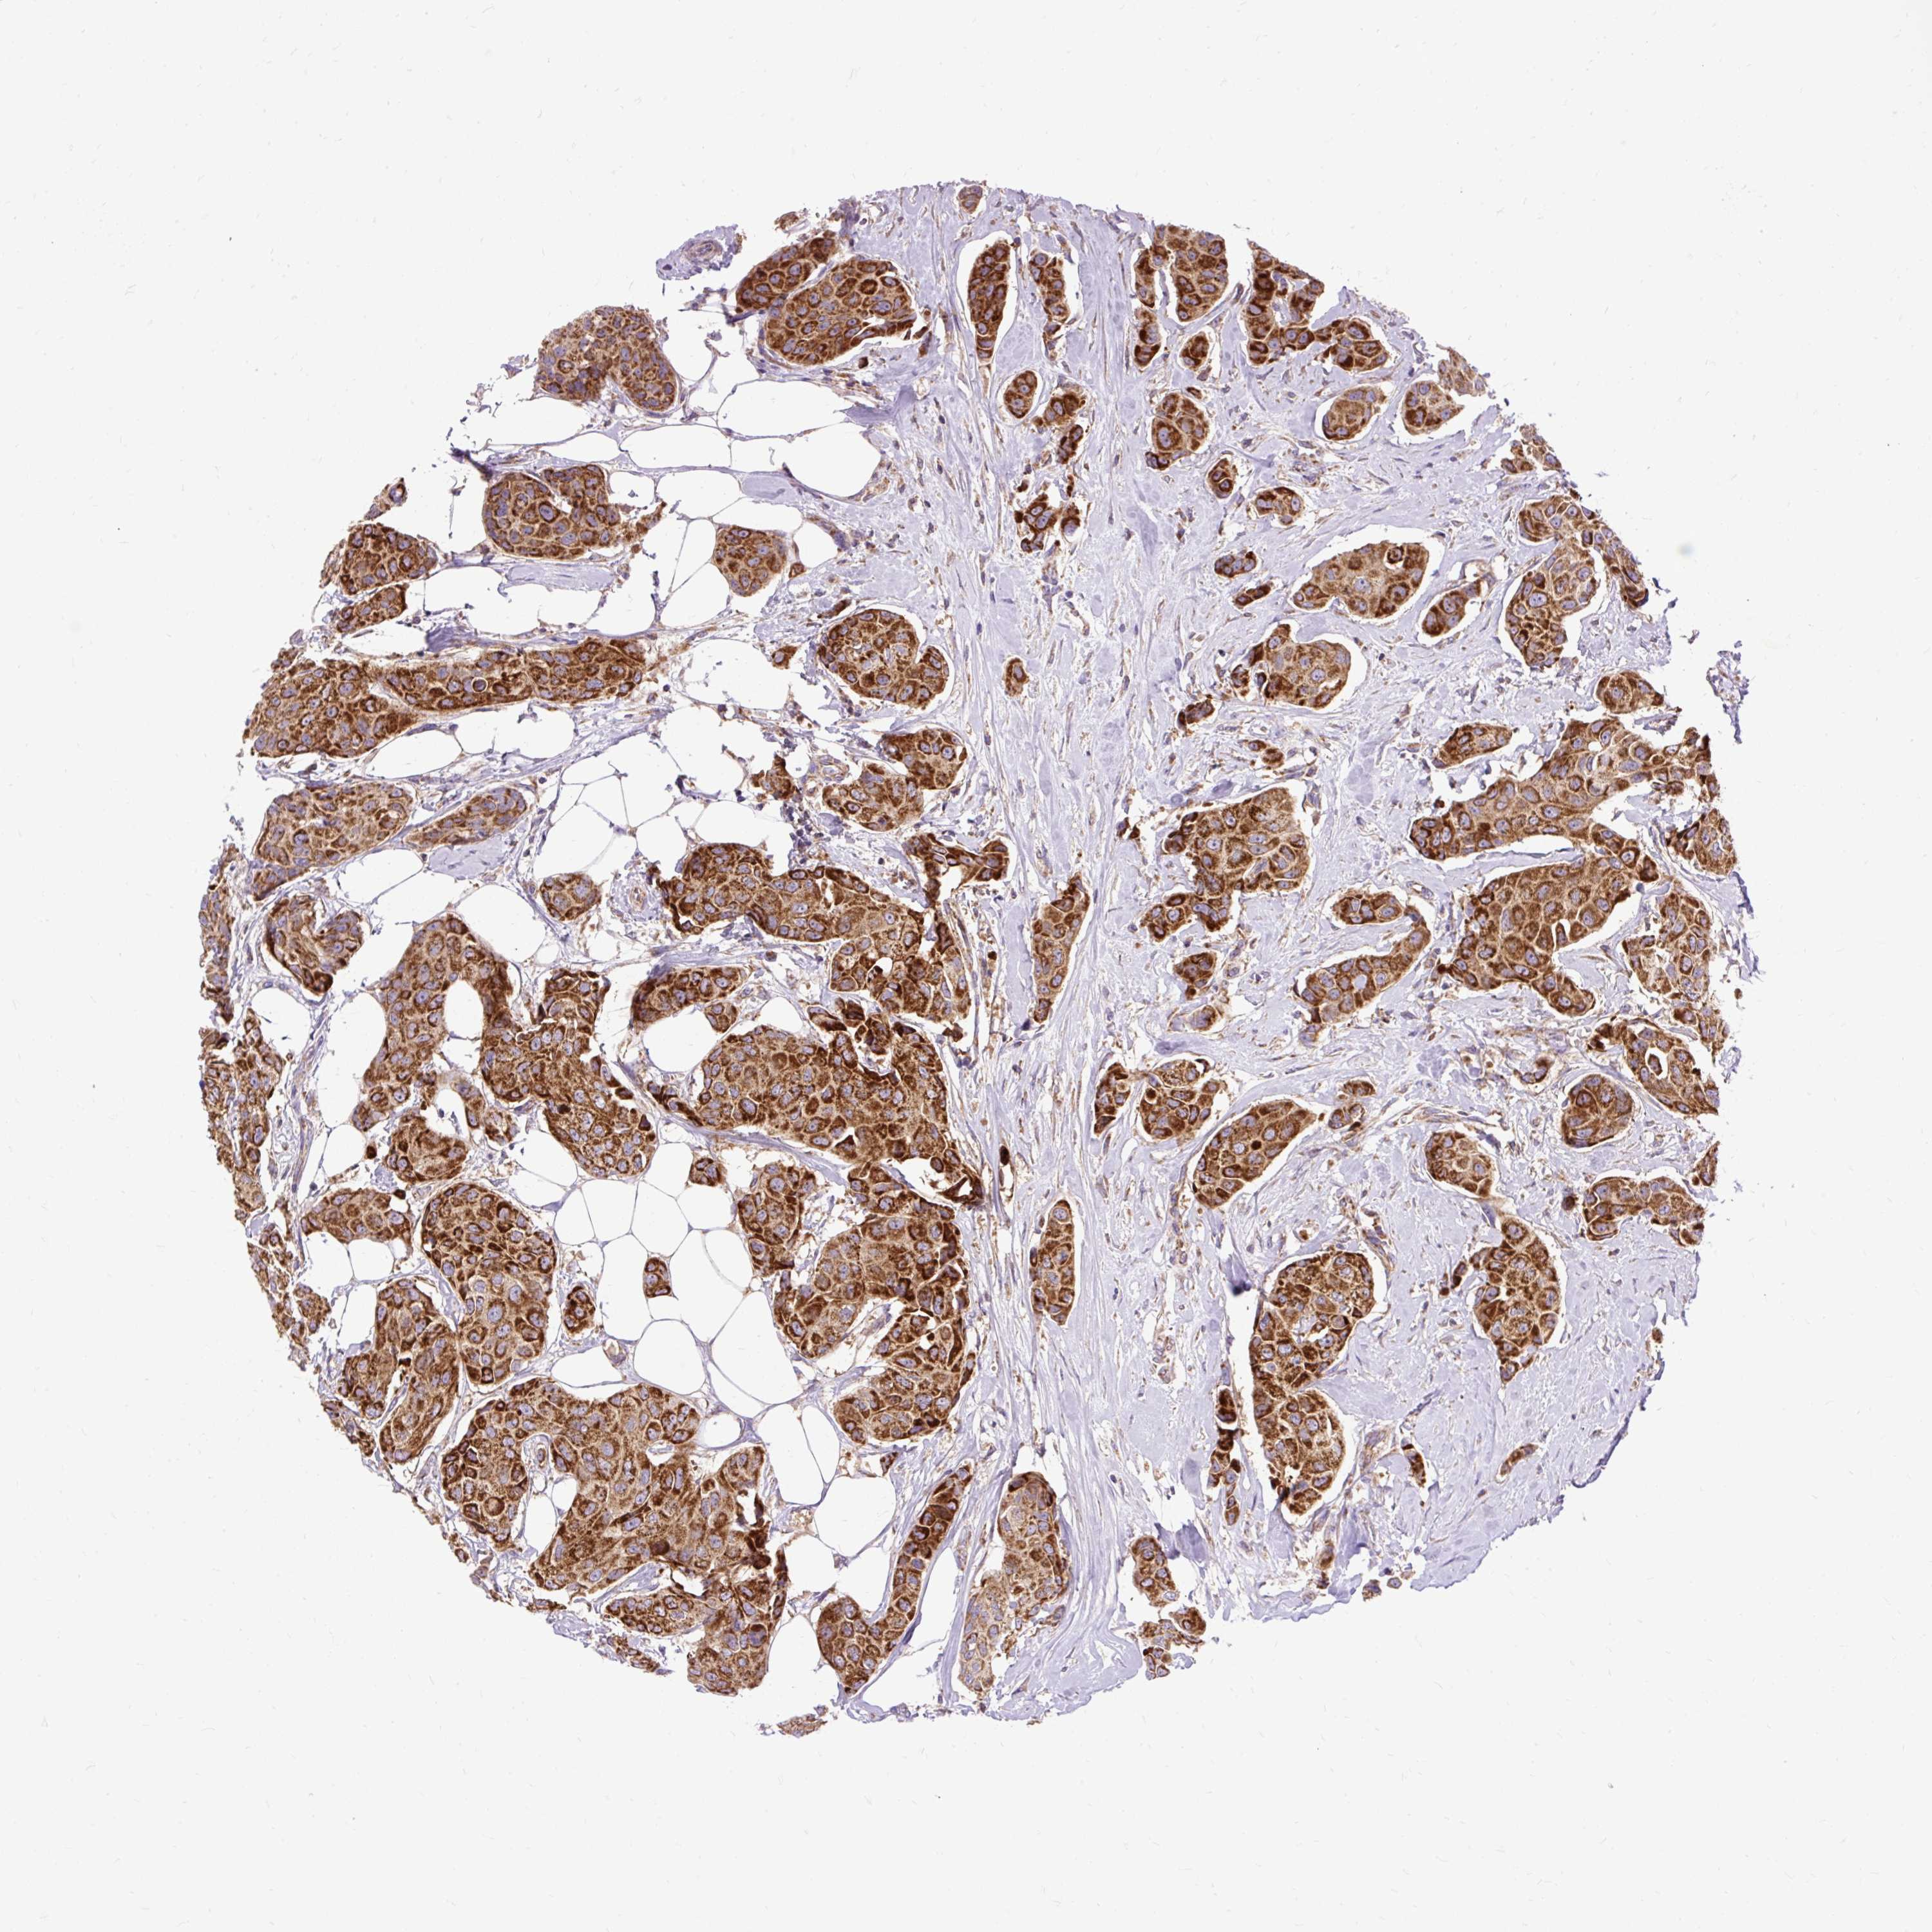

BRCA TCGA BRCA VALIDATION PROTEIN EXPRESSION

ANTIBODIES

AND

VALIDATION